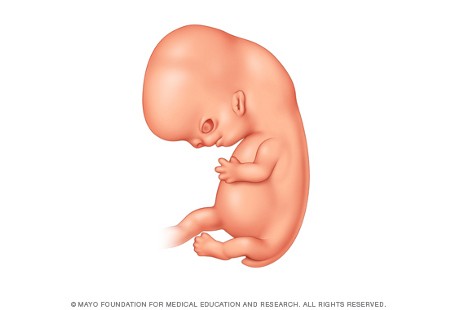

6. Minggu ke-7: Kepala Janin Berkembang

Foto: Mayo Clinic